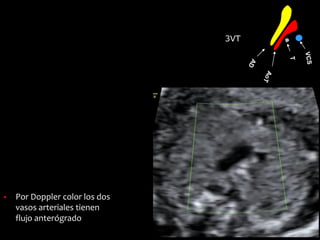

3VT

▪ La Ao transversa y el

ductus son

aproximadamente del

mismo tamaño

▪ La VCS se ve en sección

transversal a la derecha

de la Ao

▪ La tráquea está a la

derecha de los grandes

vasos, por debajo de la

VCS

▪ No hay vasos accesorios

▪ Por Doppler color los dos

vasos arteriales tienen

flujo anterógrado